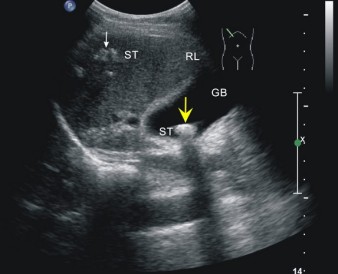

精品收藏!典型胆囊结石的三大超声特征